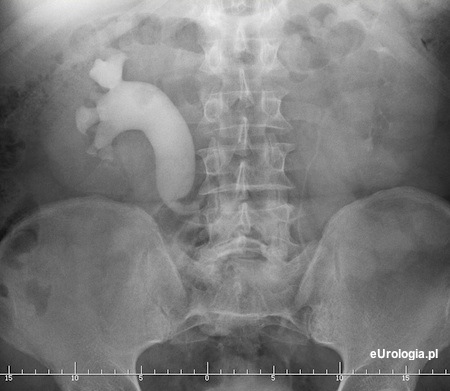

W warunkach prawidłowych moczowody przebiegają mniej więcej równolegle do dużych naczyń jamy brzusznej tj. aorty i żyły głównej dolnej. W wyniku nieprawidłowego rozwoju płodowego może dojść do powstania wady polegającej na tym, że prawy moczowód przebiega na krótkim odcinku poza żyłą główną dolną. U większości pacjentów wada przebiega bezobjawowo i nie wymaga interwencji chirurgicznej.

Fot. Zdjęcie urograficzne przedstawiające prawy moczowód przebiegający poza żyłą główną dolną - łac. Ureter retrocavalis.

W przypadku dużego wodonercza lub dolegliwości bólowych możliwe jest leczenie operacyjne. Więcej informacji można znaleźć w artykule: Operacyjne leczenie moczowodu położonego poza żyłą główną dolną.